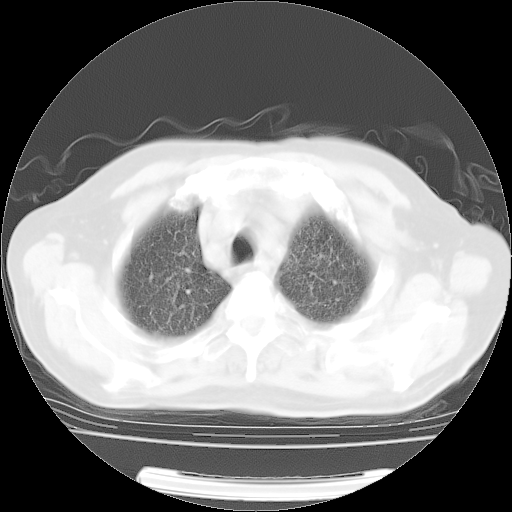

4月14日肺部CT

27.JPG

28.JPG

29.JPG

30.JPG

肺部CT平扫未见异常。